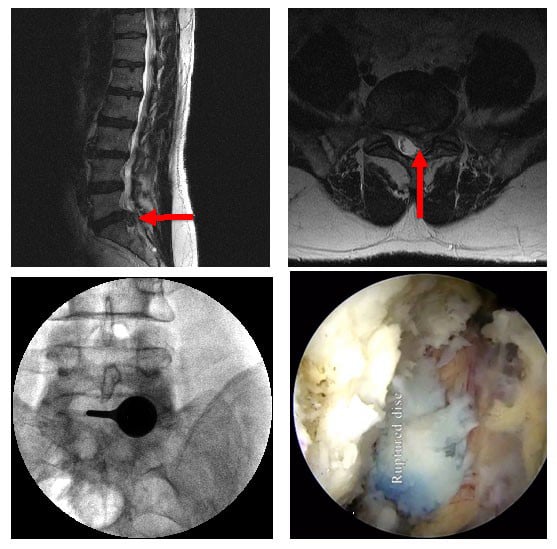

Διαστρωματική (μέσω της μέσης της πλάτης) ενδοσκοπική οσφυϊκή δισκεκτομή, με μαγνητική τομογραφία πριν από τη χειρουργική επέμβαση (πάνω αριστερά και δεξιά), ακτινογραφίες που έγιναν κατά τη διάρκεια της επέμβασης που δείχνουν την ενδοσκοπική θύρα στη θέση (κάτω αριστερά) και ενδοσκοπική όψη μεγάλης ρήξη δίσκου (κάτω δεξιά).